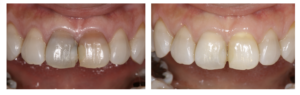

褐線が認められた近遠心に3 級コンポジットレジン修復を除去し, 再修復物を施した(図5)。

5)漂白終了3年経過後

後戻りは認められず, 患者本人の満足度も高かった.

図5 術後の口腔内写真

図6 22 歳女性 術前術後の口腔内写真